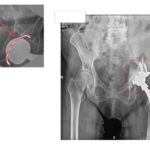

Στις εικόνα 11 και εικόνα 12 ημιαρθροπλαστική AMIS για υποκεφαλικό κάταγμα ισχίου, από προσωπικό αρχείο